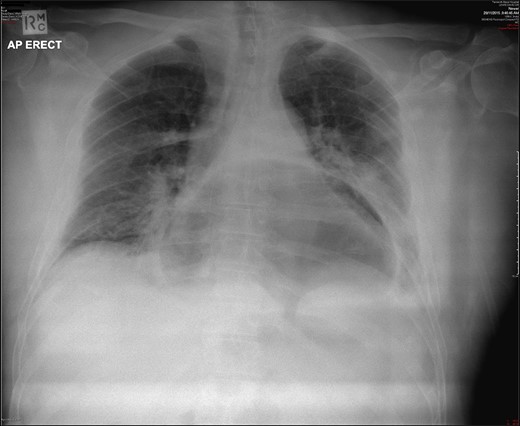

A 69-year-old man with a background medical history significant for hypertension and mild obesity, presented to his local district hospital in remote New South Wales, Australia with sudden onset of severe epigastric pain radiating to his back. He was diaphoretic and pale, and initial assessment of the patient seemed to be that of a man suffering an acute myocardial infarction. Despite this, his initial observations were all within normal limits, and his electrocardiograph revealed a sinus bradycardia and no ischaemic changes. All initial blood examinations, including serum troponin, lactate, liver function tests, renal markers, electrolytes and C-reactive protein were completely normal, with the full blood count revealing only a mild leucocytosis (12.3 × 109/L). Interestingly, the most significant finding came from his initial chest X-ray which showed a large intrathoracic gastric bubble consistent with a large hiatus hernia (Fig. 1). The patient went on to have an intravenous contrast-enhanced computed tomography (CT) scan of the chest and abdomen which revealed an obstructed intra-thoracic stomach incarcerated within a para-oesophageal hernia (Fig. 2). Surgical services in the patient’s local town are limited and thus the patient was transported to the closest regional centre with on-call general surgical services. Decompression with a nasogastric tube (NGT) was attempted but failed.